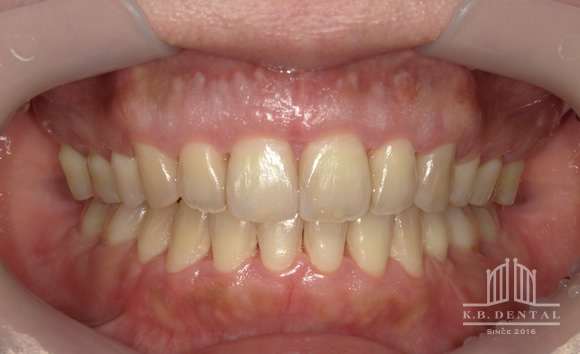

口蓋隆起 症例5(口蓋隆起形成術)

無痛治療での口蓋隆起形成術。骨ノミとピエゾサージェリーを使い、低侵襲な手術を行いました。上顎の違和感がなくなります。

料金

静脈内鎮静法による麻酔代込み:約15万円(保険適用外)

口蓋隆起 症例6(口蓋隆起形成術+親知らず抜歯)

無痛治療で口蓋隆起形成術。同時に左上の親知らずも抜歯しました。ピエゾサージェリーも使い低侵襲な手術を行いました。上顎の違和感がなくなります。